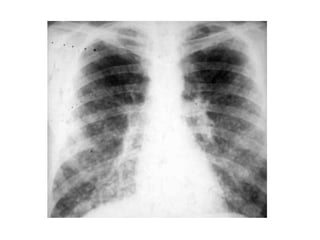

Histoplasmosis: Rx de tórax

• Linfadenopatía en mediastino

(calcificación en formas crónicas)

• Infiltrados en placas

• Con menos frecuencia:

– Cavitación

– Atelectasias por obstrucción debido al

agrandamiento de los ganglios

• En histoplasmosis diseminada patron

micronodular (semeja Tb miliar).

Histoplasmosis: Rx detórax • Linfadenopatía en mediastino (calcificación en formas crónicas) • Infiltrados en placas • Con menos frecuencia: – Cavitación – Atelectasias por obstrucción debido al agrandamiento de los ganglios • En histoplasmosis diseminada patron micronodular (semeja Tb miliar).